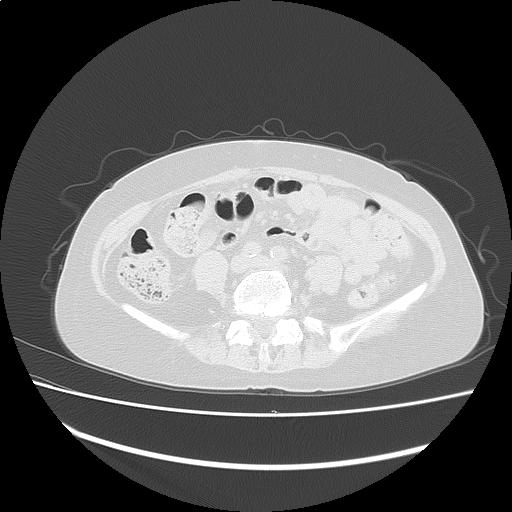

【読影指南】症例画像8

甲状腺から骨盤までスクリーニング

年齢: 72歳

性別: 女性

検査部位: 胸腹部

検査種別: CT

CTスライス画像

CTスライス1